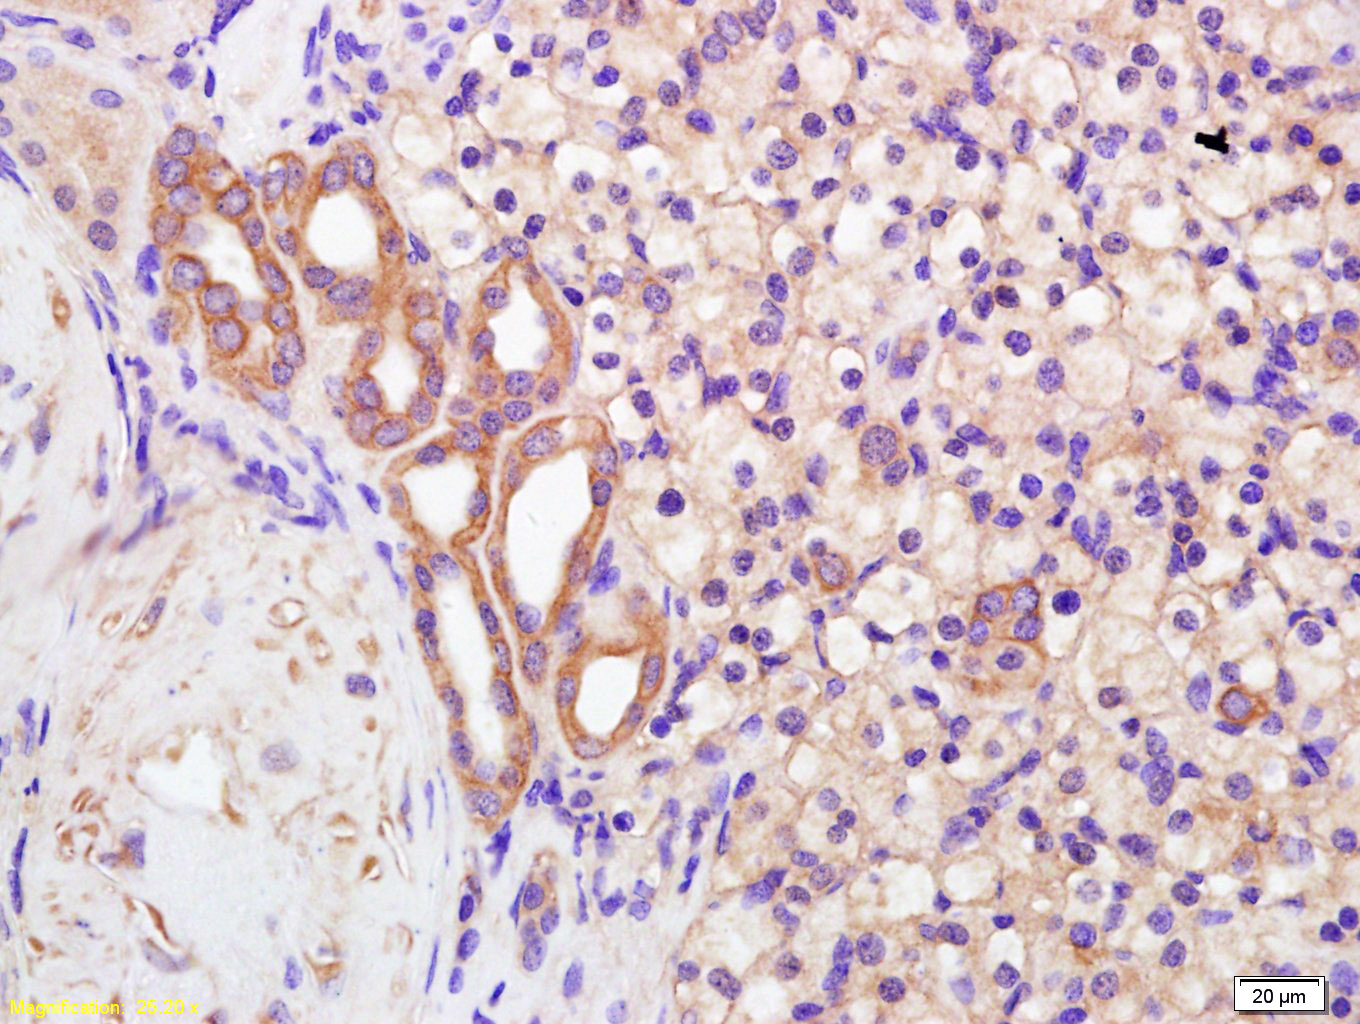

Tissue/cell: human kidney carcinoma; 4% Paraformaldehyde-fixed and paraffin-embedded;

Antigen retrieval: citrate buffer ( 0.01M, pH 6.0 ), Boiling bathing for 15min; Block endogenous peroxidase by 3% Hydrogen peroxide for 30min; Blocking buffer (normal goat serum,C-0005) at 37℃ for 20 min;

Incubation: Anti-Polycystin 2 Polyclonal Antibody, Unconjugated(bs-2158R) 1:200, overnight at 4°C, followed by conjugation to the secondary antibody(SP-0023) and DAB(C-0010) staining